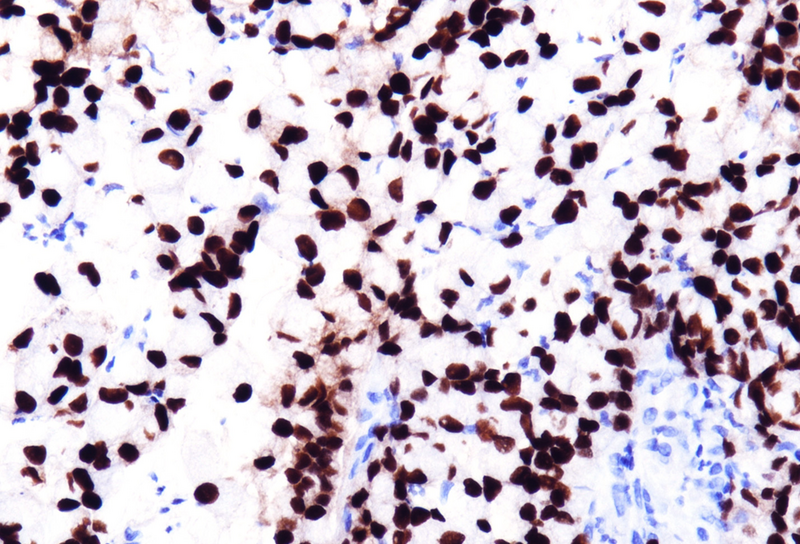

Immunohistochemistry revealed diffuse and strong cytoplasmic positivity for CK20 (Panel D), along with nuclear positivity for CDX2 (Panel E) and SATB2 (Panel F). The tumor cells were negative for CK7. Mismatch repair protein staining demonstrated complete loss of MLH1 (Panel G) and PMS2 (Panel H), while MSH2 and MSH6 expression was preserved.